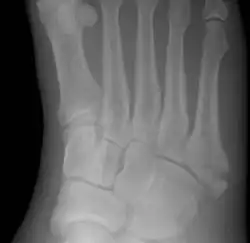

A Jones fracture is a broken bone in a specific part of the fifth metatarsal of the foot between the base and middle part .[8] In general, fifth metatarsal fractures heal readily, but a Jones fracture must be recognized and accurately diagnosed because of its higher rate of delayed healing or nonunion.[4] It results in pain near the midportion of the foot on the outside.[2] There may also be bruising and difficulty walking.[3] Onset is generally sudden.[4]

The fracture typically occurs when the toes are pointed and the foot bends inwards.[6][2] This movement may occur when changing direction while the heel is off the ground such in dancing, tennis, or basketball.[9][10] Diagnosis is generally suspected based on symptoms and confirmed with X-rays.[3]

Diagnostic X-rays include anteroposterior, oblique, and lateral views and should be made with the foot in full flexion.